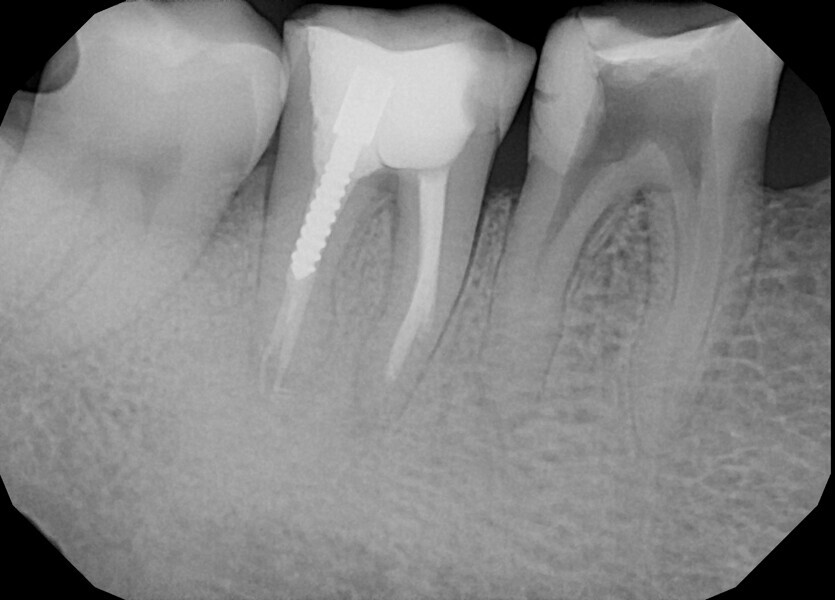

During the second appointment, sodium hypochlorite 5,25% was activated with SkyPulse in AutoSWEEPS mode for most of the treatment. It was very important that the laser tip that was placed below the root canal orifice but without touching the root canal walls. This is a very important modification of the techniques introduced by Giovanni Olivi. The standard technique of AutoSWEEPS activation requires activation of the irrigants with the laser tip above the orifice pointing in a different directions during the activation cycle. In the case of non-patent canals, placing the fibre below the orifice works in a much more effective way. After every five to six cycles of sodium hypochlorite, 17% EDTA was used. After every sequence of AutoSWEEPS activation, the canals became more patent in the deeper segments. C-PILOT files were used to enlarge the canal space. After reaching an additional 2–3 mm of the working length, the rotary file was used to enlarge the space above. This procedure may look like traditional crown-down scouting, but with AutoSWEEPS activation the hand files reached the deeper parts of the canal much more passively with watch-winding movements (30° clockwise and 30° anticlockwise) without using push–turn–pull movements (45° clockwise with constant pressure). In this case, the risk of creating false paths in curved canals is much smaller, and establishing the glide path is more predictable. Finally, patency in both mesial canals was reached and a periapical radiograph was performed to confirm this (Fig. 19). On the radiograph, it was clearly visible that both hand files had slightly bent into the S-shaped curvature, ensuring that the natural path of the canal was shaped. Despite very long irrigation with AutoSWEEPS activation, patency of the distal canal could not be achieved. Both mesial canals were shaped up to size 30/0.04 with Endostar E3 Azure files.

After irrigation with 5.25% sodium hypochlorite and 17% EDTA, the canals were filled with an epoxy resin sealer and warm gutta-percha using the continuous wave compaction technique. A periapical radiograph was performed to confirm obturation (Fig. 20). The pulp chamber was filled with composite resin reinforced with fibre posts, and the tooth was referred for final restoration with cusp coverage.